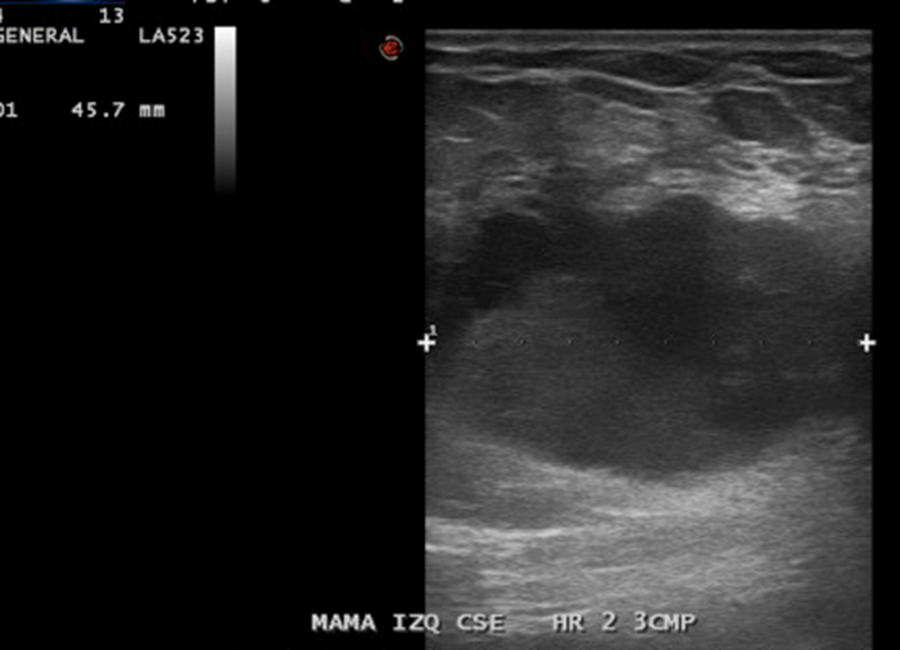

En Mama IZQ CSE HR 2, a 3 CMP, imagen nodular hipoecogénica, ovalada, 31 x 36 x 26 mm.

• La mama izquierda presenta en el cuadrante supero-externo, eje horario 2, a 3 cm. del pezón, imagen nodular hipoecogénica, bien definida, ovalada de 36 x 26 x 31 mm., sugerente de lesión quística con contenido, no vascularizado. Esta lesión presenta escaso refuerzo acústico posterior.

Impresión: Lesión sugerente de quiste con contenido en mama izquierda, se recomienda control evolutivo. BIRADS US 3.